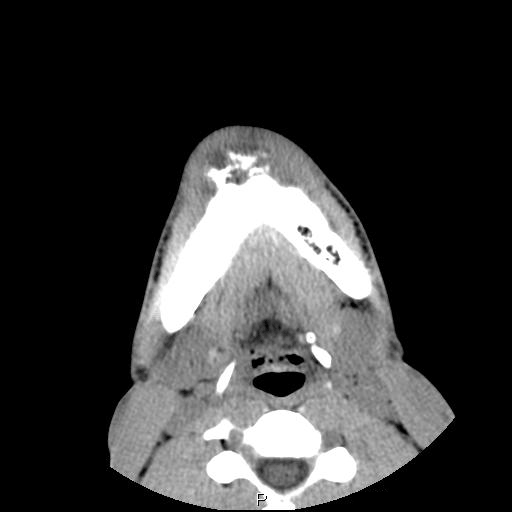

Clinical information The patient was a 23 year-old man who went to see the dentist because of dull pain, swelling of the chin,  and loosened lower front teeth. He was referred to this hospital after initial examination. A CT scan was performed and and a biopsy was taken. Representative images are presented here. Panel D is a sagittal reconstruction from axial CT scans. A resection was subsequently performed.

A. B. C. D.

CT scan: On the CT scan images (Panel A, B, C, and D), two lesions are present.  There is a lesion at the mental protuberance that appears to have penetrated the cortex and invaded into the soft tissue. The patchy hyperdensity strongly suggests that this lesion has mineralize elements ( in Panel B). The border of the lesions in the mandible is poorly defined. The penetration of the bone and extension into the soft tissue is best appreciated in the sagittal reconstruction in (Panel D). These features are highly suggestive of a malignant neoplasm that originates from the bone with extension into surrounding soft tissue. The hyperdensity of the mass suggests bone formation and the radiologic features are suggestive of an osteosarcoma. In the right body of the mandible, there is a diffusely expansile lesion  with some hazy hyerdensity (Ú in Panel B). The cortical bone overlying this lesion is intact. This lesion may represent extension of the osteosarcoma into the body. However, it may also represent a co-existing fibrous dysplasia.